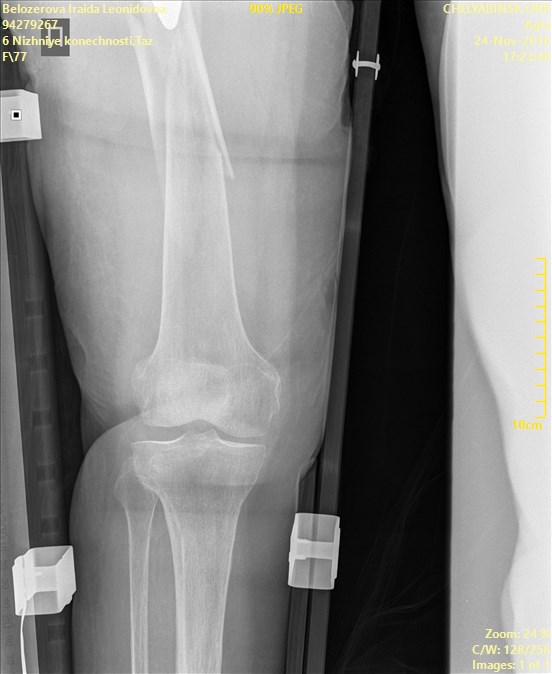

ÎÏÖËÁ   ó÷î   10(ã×ÁÊÍÀÌÌÅÒ)íÁÔÉÓ.   ðÏ   ÎÁÛÉÍ   ÉÚÍÅÒÅÎÉÑÍ  ÏÔ

ÍÅÖÍÙÝÅÌËÏ×ÏÊ ×ÙÒÅÚËÉ ÄÏ ËÏÎÃÁ ÎÏÖËÉ 204ÍÍ. îÏÇÁ ÐÒÁ×ÁÑ

Name: Belozerova_Iraida_Leonidovna_TAZO-BEDRENNYI_AP_CR.jpg